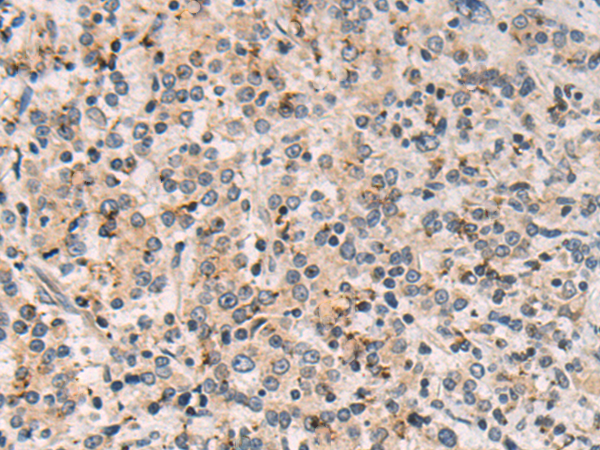

分类: 科研抗体货号: P10615别名: MLC1SA应用: IHC反应种属: Human, Mouse